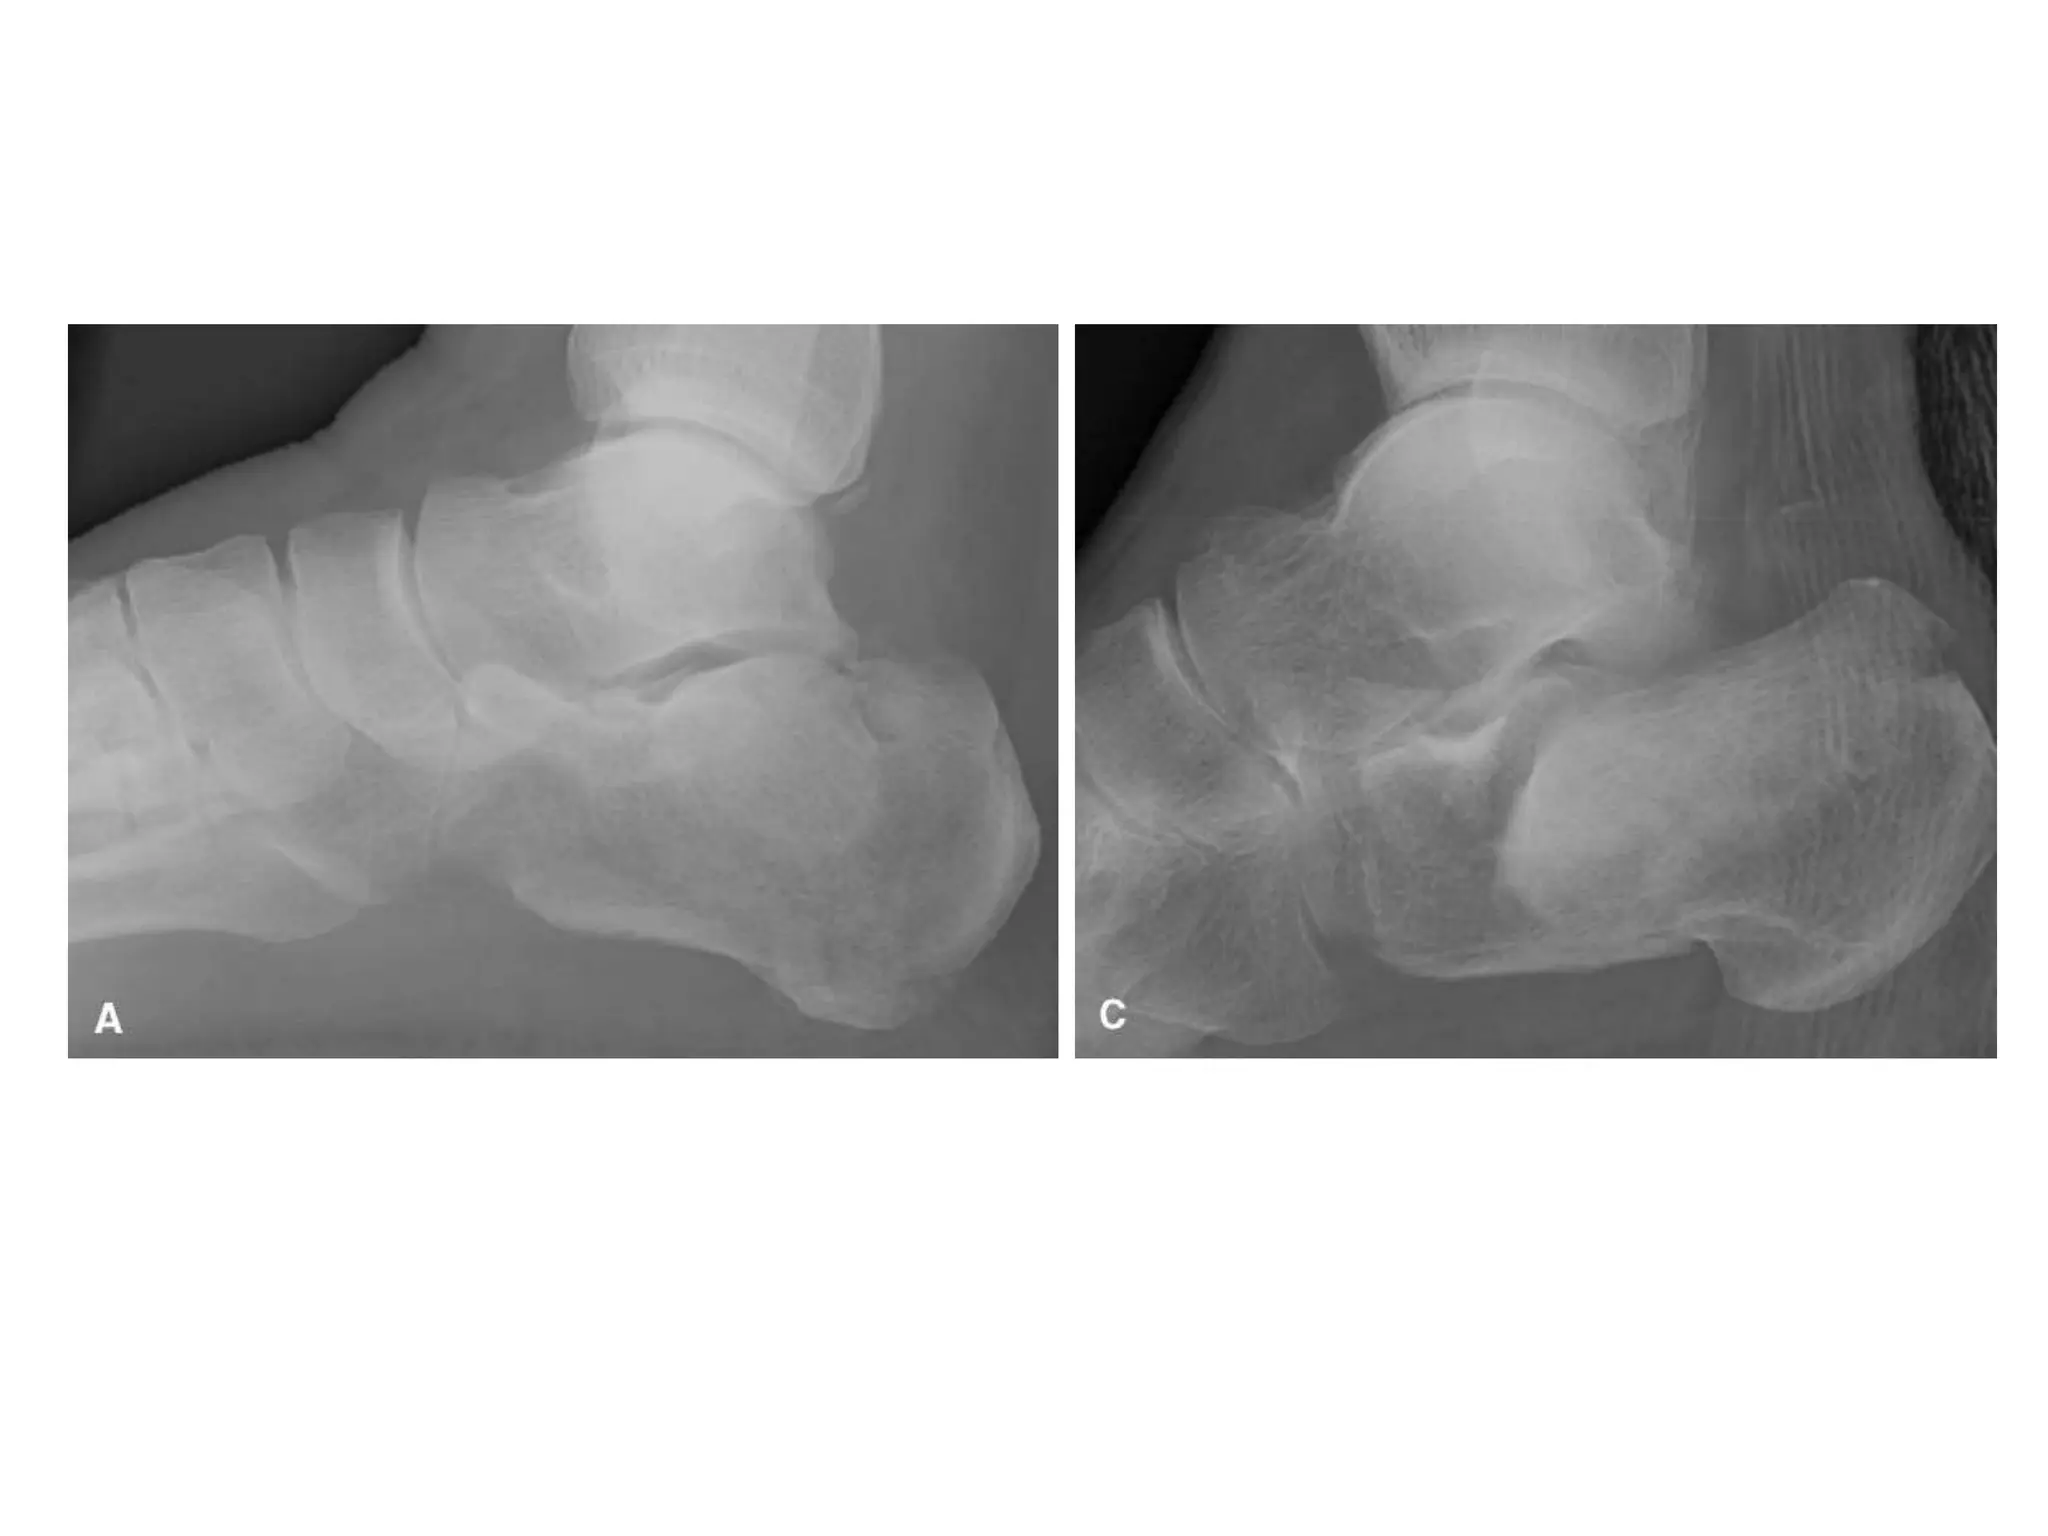

RADIOGRAPHIC ANATOMY

Lateral radiograph

Bohler’s Angle

Gissanes angle

“Double density” sign

Shows joint-depression or

tongue-type

The “double density”; a joint-depression–type fracture where the lateral portion of

thejoint is impacted but both Böhler and Gissane angles are normal

Ap radiograph

Extension of fracture line into CCJ

Harris axial view

Angulation of the tuberesity

Height of calcaneous

Width of the calcaneous

Broden view

Visualizes articular surface of the posterior facet on

plain radiographs

CT scan

Axial, 30-degree semicoronal, and sagittal planes